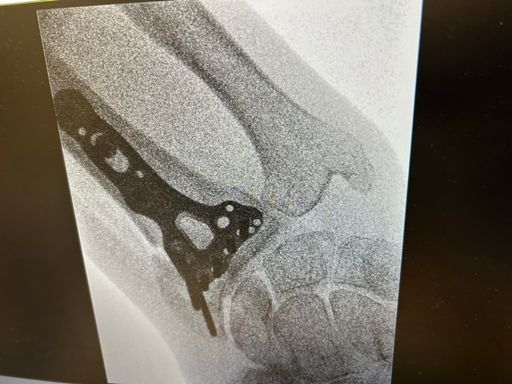

Physio on the Peloton. 2 weeks after surgery 30 min Vinyl Vault Ride with Hannah Corbin